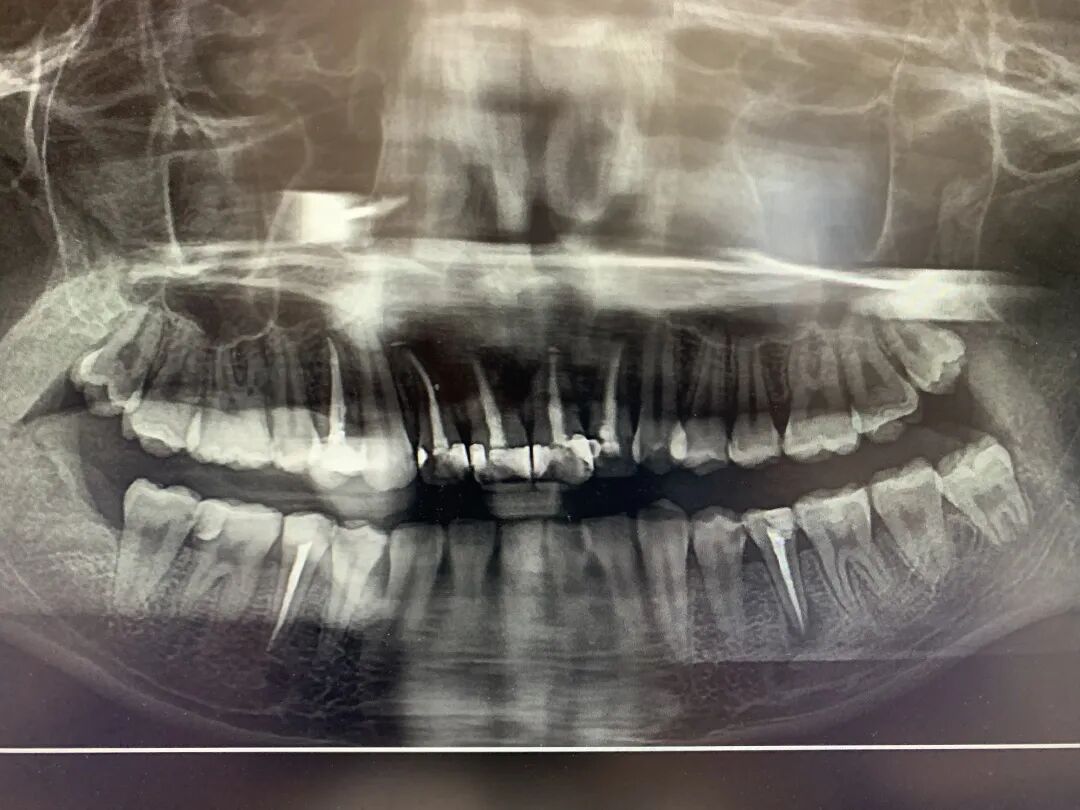

牙齿治疗的记录 | 图源作者

令我破费的一口牙 | 图源作者